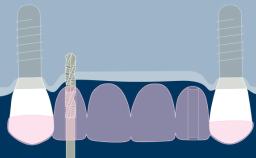

Prosthodontically driven implant planning ensures that implant placement is compatible with the desired end result, which is a key factor for successful outcomes in implant therapy.

Digital technologies now available in the field of implant dentistry facilitate prosthodontically driven implant planning. Benefits of these technologies include significant improvements in patient assessment and treatment planning, allowing clinicians to position supporting implants with a high degree of accuracy.